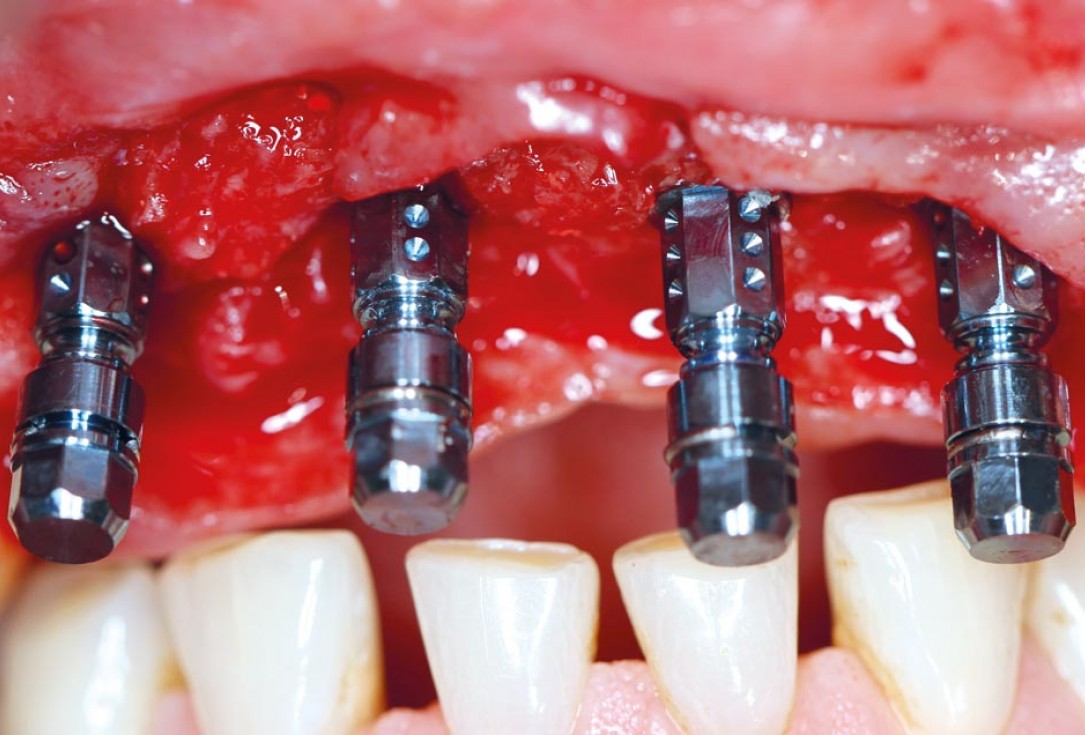

3/17 - Complex bone defect with partial loss of the buccal wall after implant extractionRestoration of all four incisors with maxgraft® bonebuilder - Dr. Dr. Dr. O. Blume